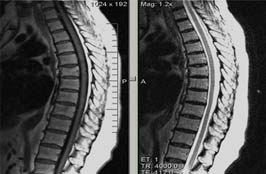

Перелом тела th12

Перелом тела th12 116 фотографий